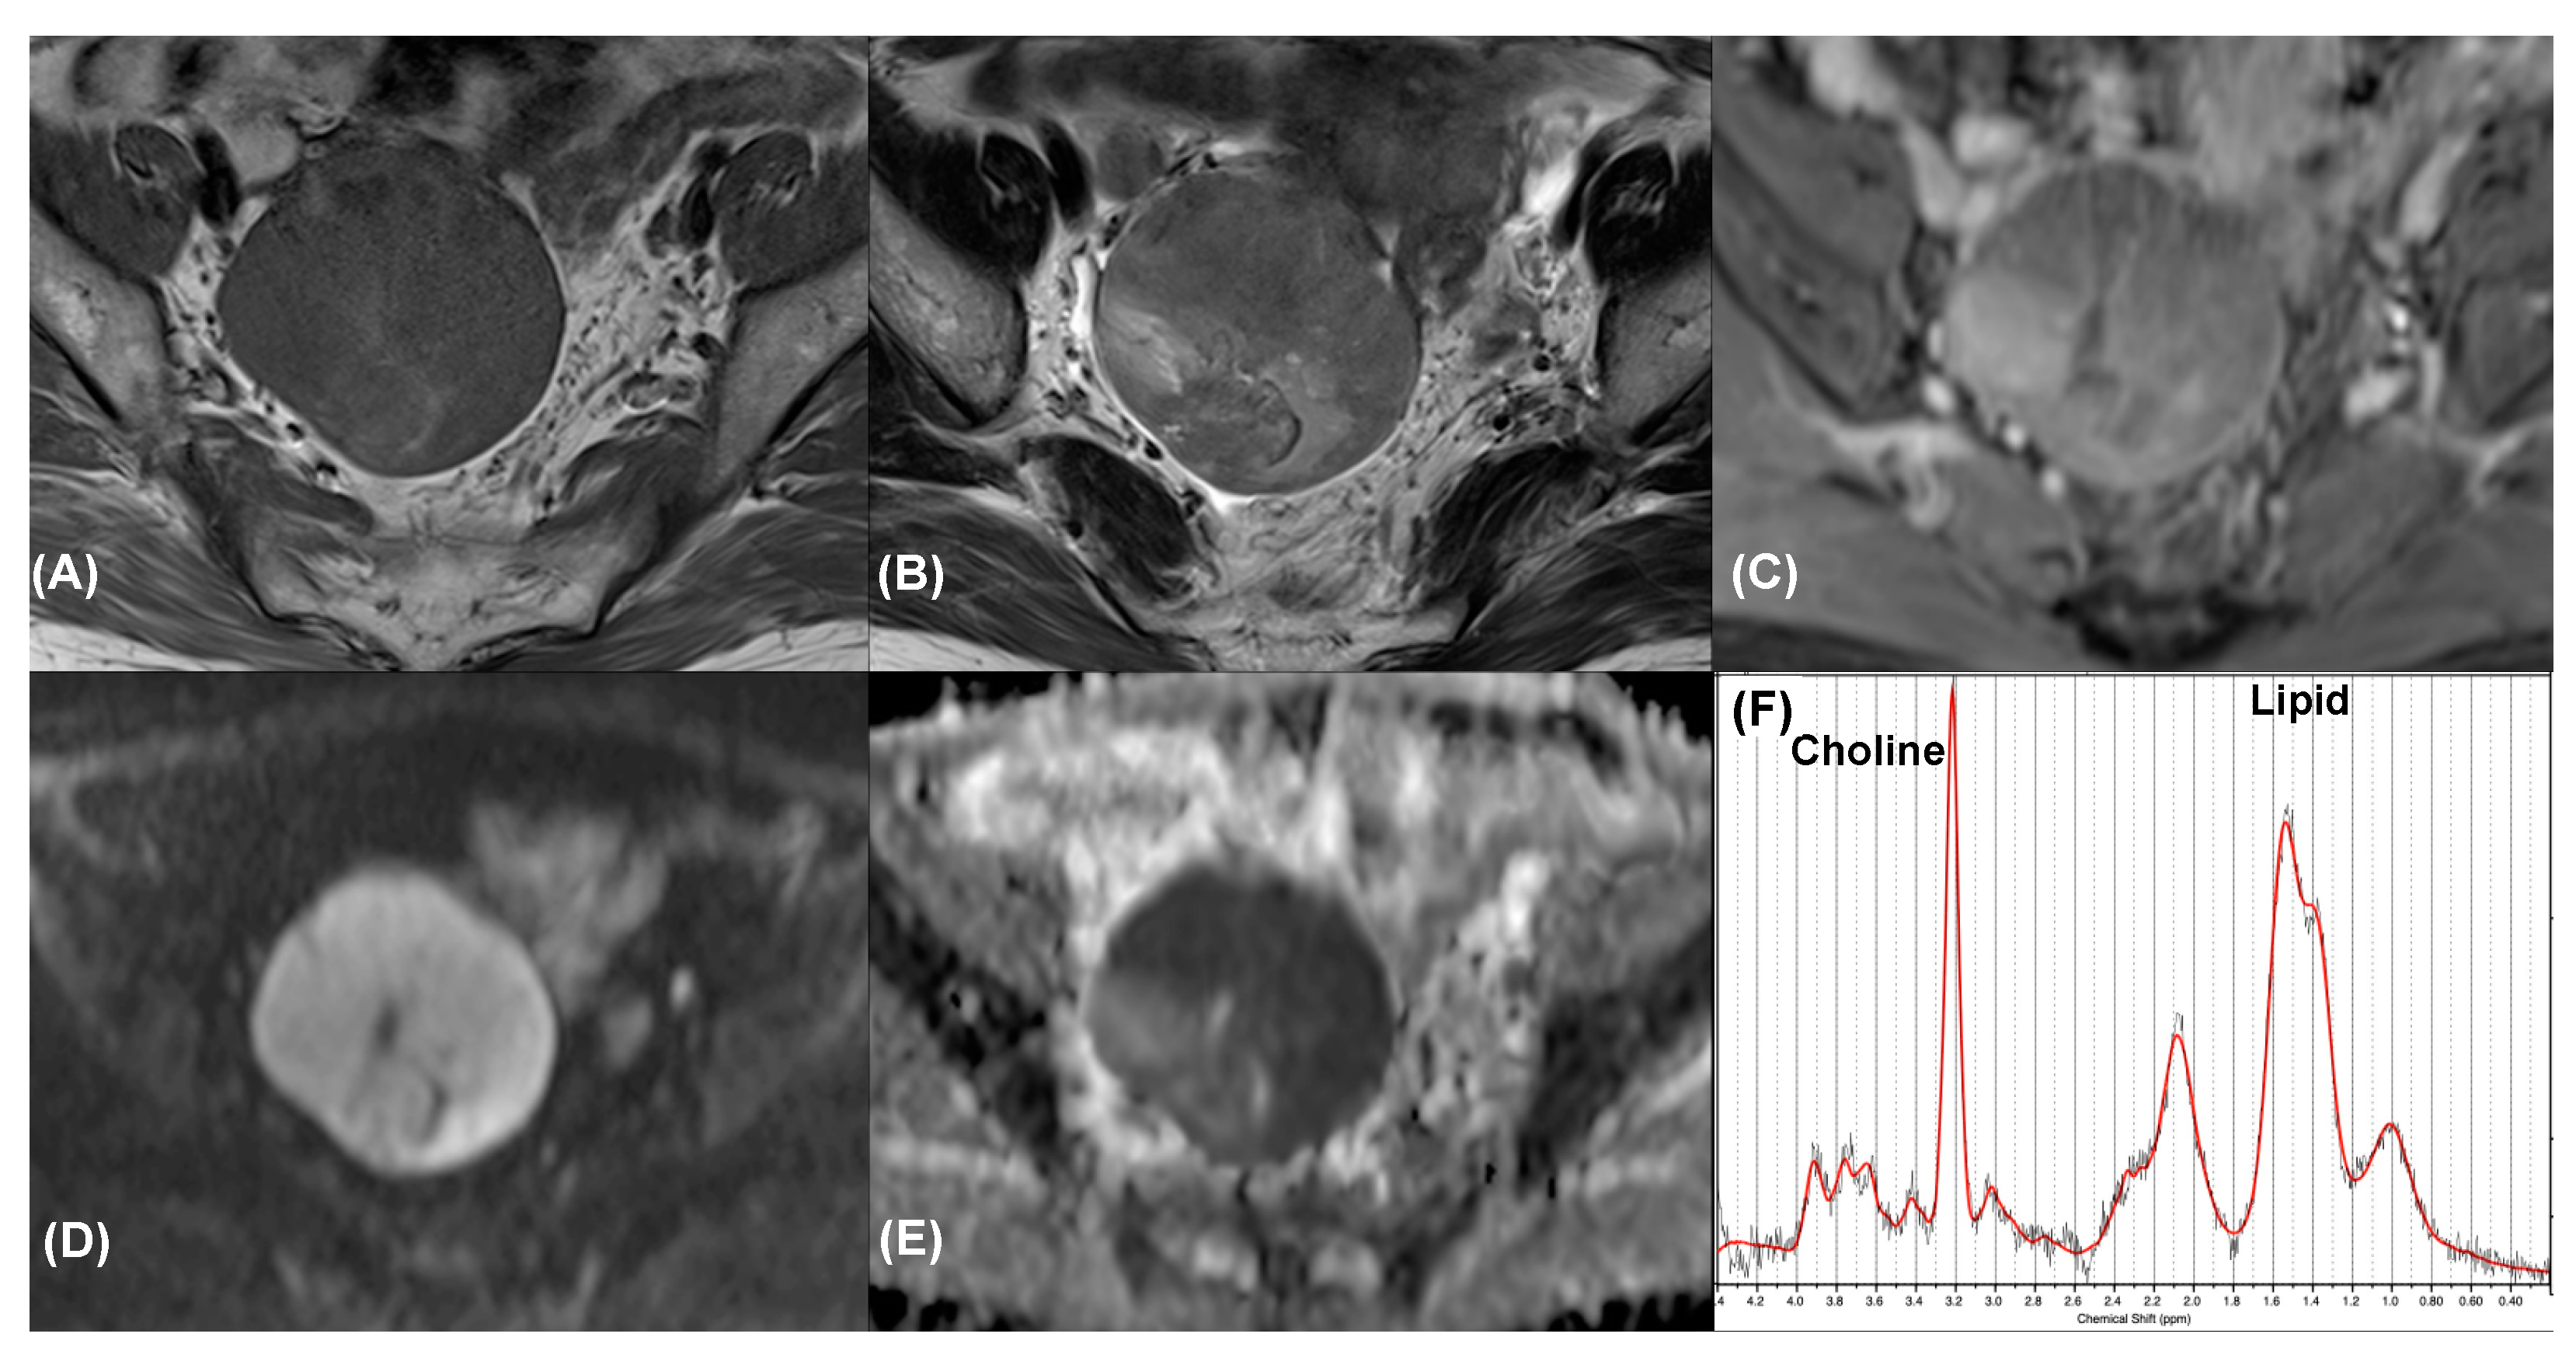

Figure 3.

Synchronous endometrioid cell carcinoma in a 55-year-old woman with endometrial cancer. Axial (A) T1-weighted, (B) T2-weighted, and (C) contrast-enhanced T1-weighted MR images show a right adnexal tumor with solid portion enhancement. Axial (D) high-b-value DW image (b = 1000 s/mm2) and (E) ADC map demonstrated marked restricted diffusion of the tumor. The tumor was classified as an O-RADS 4 lesion. (F) MR spectroscopy depicts choline and lipid peaks (SNR = 20.0 ± 1.8; linewidth = 8.2 ± 1.2 Hz). Data are in black, and the corresponding fit is in red.